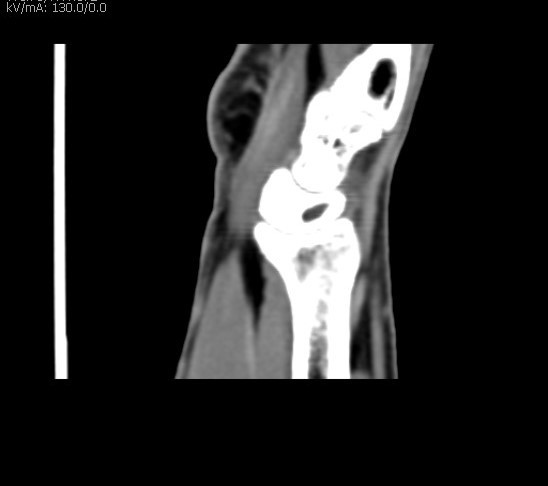

Exames de tomografia são muito confiáveis e seguros, realizados por aparelho de raios X de alta resolução que gira em torno do corpo, fazendo radiografias transversais. É capaz de obter imagens em fatias do corpo, gerando imagens tridimensionais. O exame é indolor, o paciente deve permanecer imóvel e é de rápida duração.